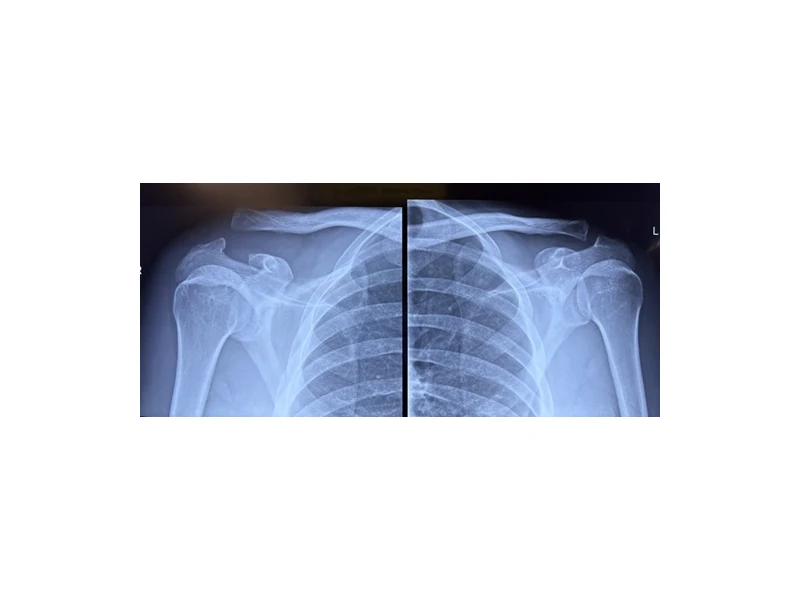

Η διαγνωση τίθεται με την λήψη ιστορικού, κλινική εξέταση και ακτινολογικό έλεγχο με ακτινογραφία του τραυματισμένου και του υγιή ώμου, για σύγκριση. Σε ορισμένες περιπτώσεις διενεργείται και αξονική ή μαγνητική τομογραφία, για λεπτομερή καταγραφή ενδεχομένως άλλων συνοδών κακώσεων.